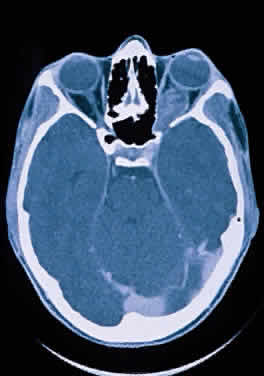

Computed tomographic (CT) and magnetic resonance imaging (MRI) have had a significant impact on the management of patients.29 Many tumors are diagnosed based on imaging features alone, without tissue confirmation (Fig. 35). They typically show a demarcated fusiform enlargement of the nerve, which may be kinked and indent the globe. On T2-weighted MRI, a circumferential component surrounds a compact core of low signal intensity.23 MRI is particularly useful in assessing the extent of the lesion.

Fig. 35. Computed tomographic scan showing left optic nerve glioma.